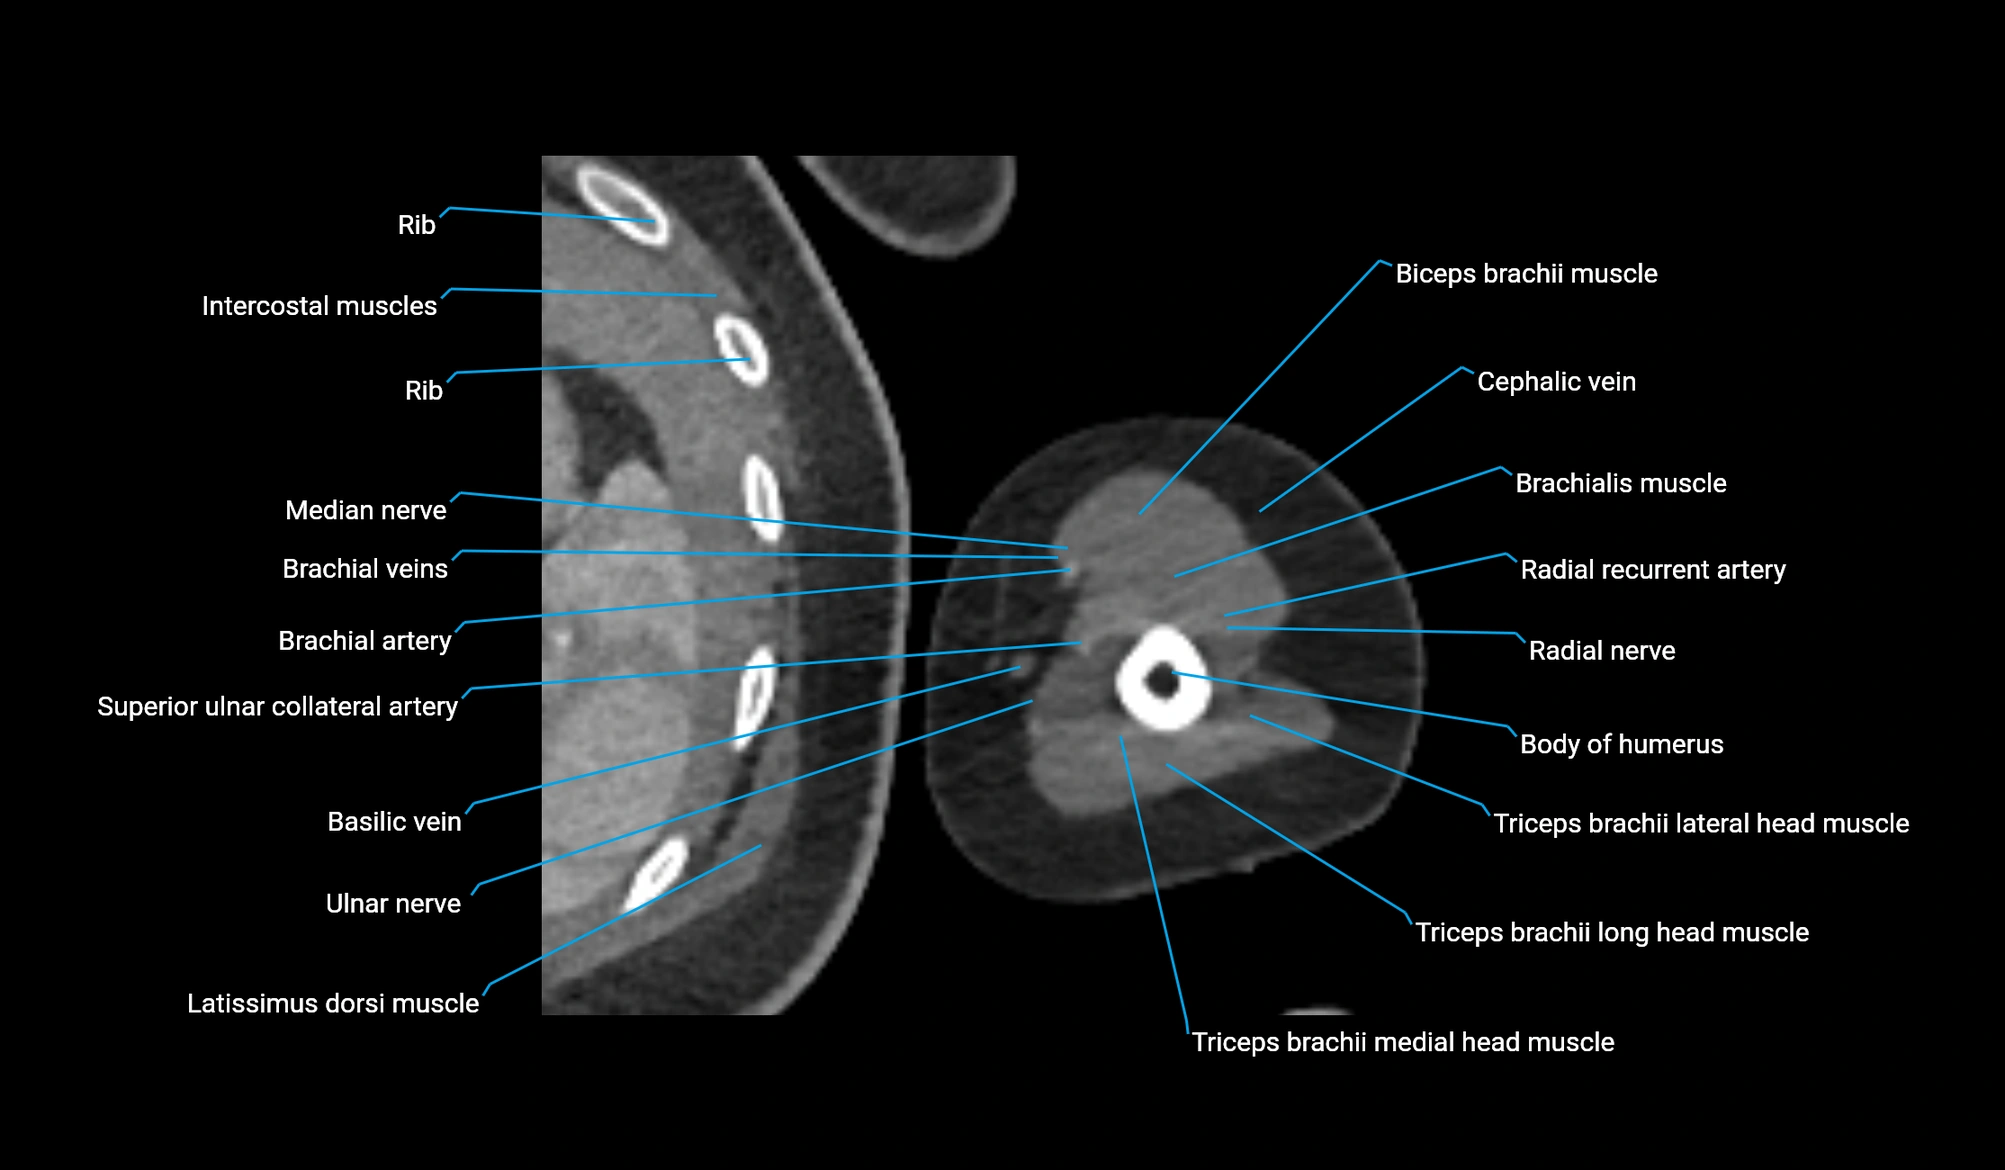

CT image